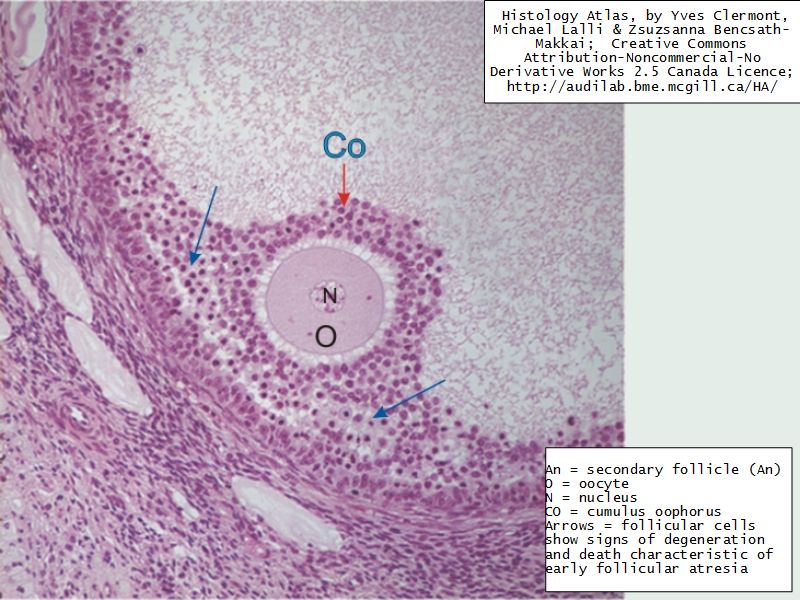

Ovaries

Slide 24

Section of the ovary

1. Outer covering. 1'. Attached border. 2. Central stroma. 3. Peripheral stroma. 4. Bloodvessels. 5. Vesicular follicles in their earliest stage. 6, 7, 8. More advanced follicles. 9. An almost mature follicle. 9'. Follicle from which the ovum has escaped. 10. Corpus luteum.

Ovary

- Capsule covered by modification of peritoneum

- Called germinal epithelium

- Simple squamous/cuboidal

- Subdivided

- Not clearly defined

- Cortex - contains ovarian follicles

- Medulla - vascular

Follicular maturation

- Primordial follicle

- Growing follicle

- Primary follicle

- Secondary follicle

- Mature follicle (Graafian)

Components of a follicle

- Theca

- externa

- interna

- basal lamina

- Granulosa cells

- Antrum

- Cumulus oophorus >> Corona radiata

- Oocyte